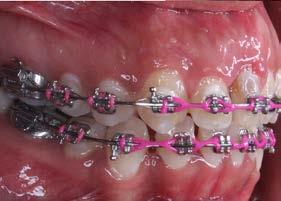

En la fase de alineación se utilizó una secuencia de arcos comenzando con el arco 0.012” NiTi, 0.014” NiTi y 0.016” Niti. Se realizó la tracción del diente 21 y se mantuvo en boca hasta comenzar la fase de trabajo, posteriormente se realizó la extracción (Figura 3).

Durante la fase de trabajo se realizaron sets de intrusión y utilización de close coil; una vez cerrado el espacio entre los incisivos laterales, se indicó el uso de elásticos de clase III 3/16 4.5 oz para corregir la mordida borde a borde (Figura 4).

3. Fotografías intraorales de avance con el central aun en boca.

Figura 4. Fotografías intraorales de avance con close coil y elásticos.

Figura